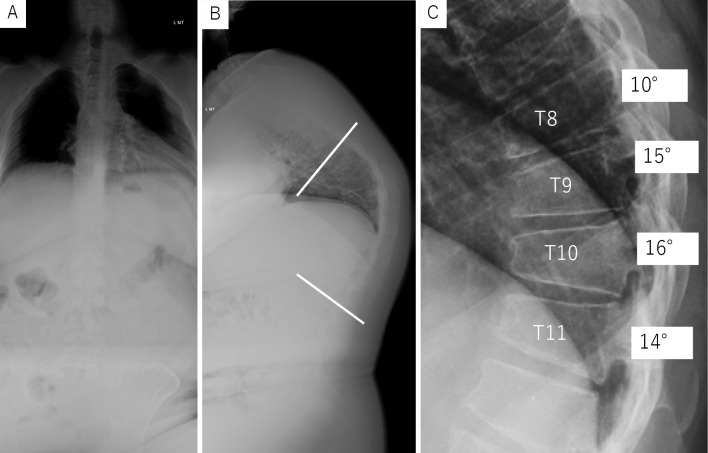

Thoracic Myelopathy with Scheuermann's Disease and Ossification of the Yellow Ligament: A Case Report.